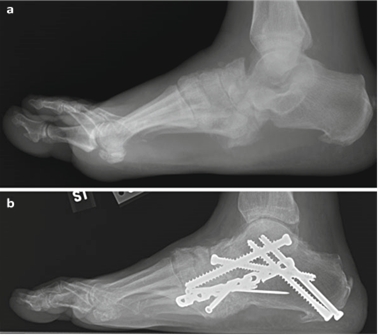

Weight-bearing anteroposterior (AP), lateral, and sesamoid axial radiographs are mandatory. On the AP view, the surgeon measures the Hallux Valgus Angle (HVA, normal < 15°), the Intermetatarsal Angle (IMA, normal < 9°), and the Distal Metatarsal Articular Angle (DMAA). The lateral view is scrutinized for Meary's angle (talo-first metatarsal angle) to identify midfoot collapse, as well as the presence of dorsal osteophytes indicative of hallux rigidus. The sesamoid axial view is critical for assessing the degree of sesamoid subluxation and the integrity of the crista.

Image